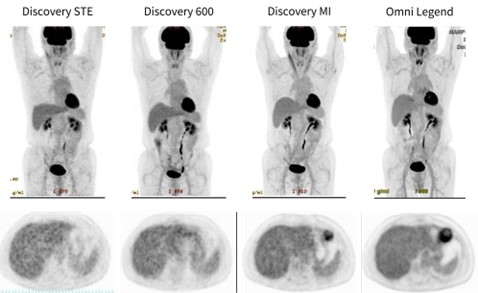

画像診断センター開設当初の 2006 年 11 月に GE HealthCare 社製 Discovery ST Elite 16 を導入し、その約 4 年後の 2010 年 7 月には 2 台目として GE HealthCare 社製 Discovery PET/CT 600 Motion を導入しました。その後、2022 年 3 月に GE HealthCare 社製 半導体 PET/CT 装置 Discovery MIへ更新し、さらに2025年1月にはGE HealthCare社製 半導体PET/CT装置Omni Legend へと更新しております。同一患者を異なる 4 機種で撮影した画像を並べて比較すると、新しい装置になるにつれて画質が向上していることが一目で分かります。特に Omni Legend では、撮影時間が短縮されているにもかかわらず、ノイズの少ない高画質な画像を得ることができています (図 2)。

図 2. 同一患者を異なる 4 つの PET/CT 装置で撮影した画像